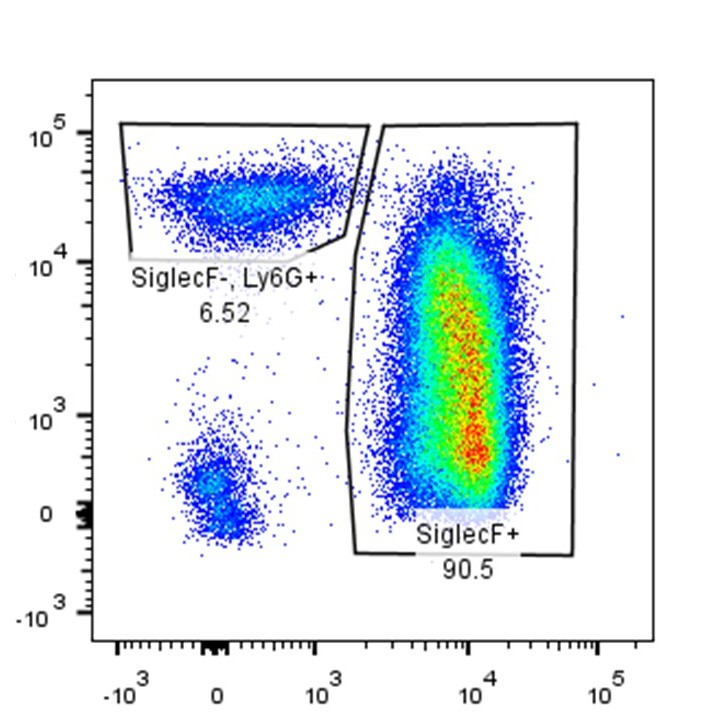

A third major pillar of my research focuses on the mechanisms that drive cardiac valve remodeling and degenerative valve disease. My work has demonstrated that mechanosensitive signaling through the ion channel PIEZO1 alters serotonin receptor pathways and promotes collagen synthesis in human mitral valve interstitial cells, linking biomechanical forces to fibrotic valve remodeling.

To extend these findings in vivo, I developed a murine model of serotonin transporter–dependent mitral valvopathy and established key experimental approaches for quantitative assessment of mitral valve structure and function in mouse models. Together, these platforms enable integrated investigation of cellular signaling, tissue remodeling, and disease progression in the mitral valve.

Collectively, these studies provide a mechanistic and translational framework for understanding degenerative mitral valve disease and for designing targeted interventions aimed at modulating mechanosensing, serotonin signaling, and fibrotic remodeling.